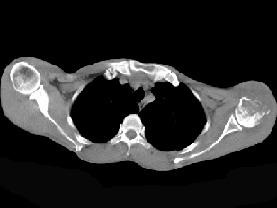

问题 患者,男,29岁,行走时不慎跌倒,曾拟为左肱骨头骨折并行固定,但半年后疼痛未减轻,触压局部骨质松软,如触及乒乓球感,明显叩击痛,请结合所提供图像,选择最佳答案 ( )

选项 A、骨转移瘤 B、骨结核 C、骨网状细胞肉瘤 D、左肱骨头骨折 E、化脓性骨髓炎

答案 C